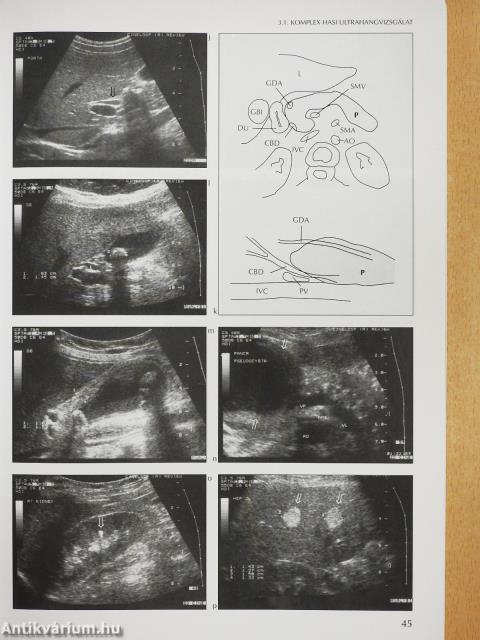

Megjegyzés: Harkányi Zoltán szerkesztő által dedikált példány. Fekete-fehér fotókkal, ábrákkal illusztrálva.

Komplex hasi ultrahangvizsgálat42